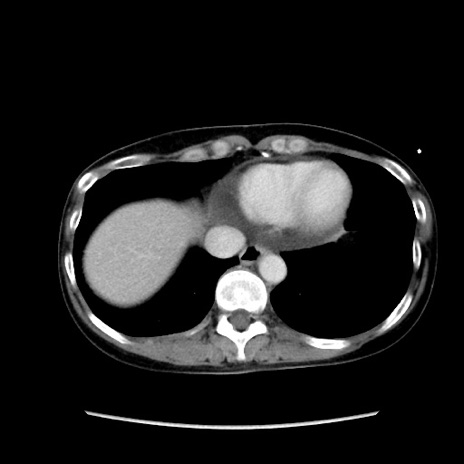

矢状断像

【症例】40歳代 女性

【主訴】上腹部痛、嘔気・嘔吐

【現病歴】約9時間前頃から急に上腹部痛、嘔気、嘔吐が出現。改善しないため救急要請。

【既往歴】子宮頚癌(広汎子宮全摘術、放射線療法)、腸閉塞

【身体所見】腹部:平坦、軟、腸雑音亢進、上腹部を中心に腹部全体に圧痛あり。

【データ】WBC 8400、CRP 0.03